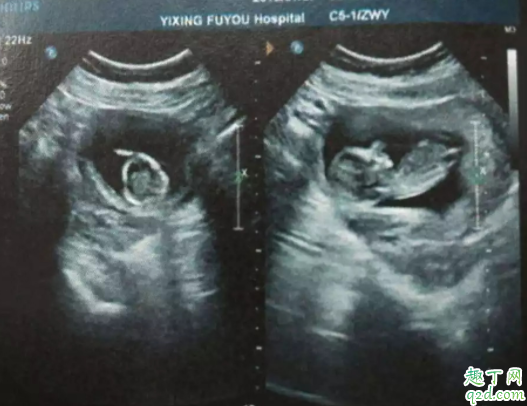

所以若有孕婦發(fā)生先兆流產(chǎn)跡象,建議到醫(yī)院做子宮和輸卵管的全面檢查(檢測孕酮值和hcg值),逐一排查原因。

如果孕酮值較低,但無陰道出血和腹痛癥狀,彩色多普勒超聲顯示胎兒正常,則無需擔心,心理壓力也是導致流產(chǎn)的因素之一。早期流產(chǎn)最常見原因是胚胎或胎兒染色體異常,只有少數(shù)患者因激素缺乏所致。